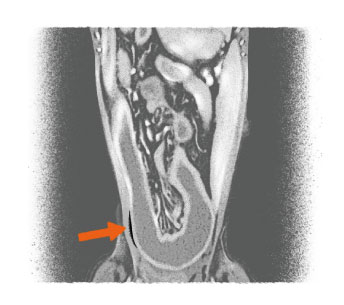

자두씨 이물 섭취

치료 후 (자두씨 제거 모습)